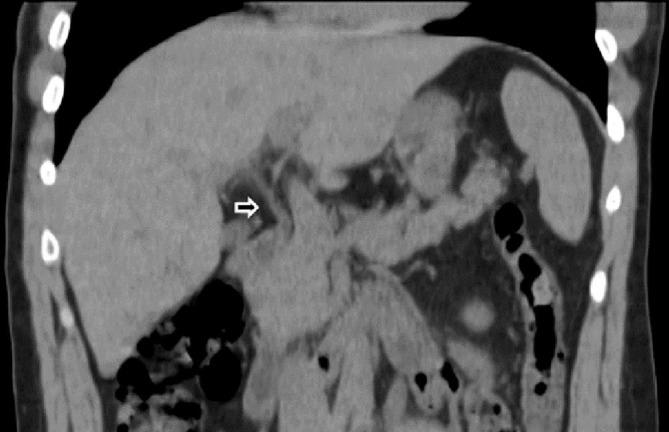

COVID-19 was first recognized by the World Health Organization (WHO) in December 2019 and declared a global pandemic in March 2020. Although COVID-19 primarily results in pulmonary symptoms, it is becoming apparent that it can lead to multisystemic manifestations. Liver damage with elevated AST and ALT is seen in patients with COVID-19. Although the etiology of liver damage is still debated, biliary damage is rarely seen. This case demonstrates a potential complication of COVID-19 in a previously healthy patient. The patient contracted COVID-19 in March 2020 and endured a complicated course including intubation, multiple readmissions, and chronic abdominal pain. He is now awaiting a liver transplant. Our case portrays biliary damage as an additional possible complication of COVID-19 and the importance of imaging in its diagnosis.

新型冠状病毒肺炎(COVID-19)于 2019 年 12 月被世界卫生组织(WHO)首次确认,并于 2020 年 3 月宣布为全球大流行。尽管 COVID-19 主要表现为肺部症状,但越来越明显的是,它可能导致多系统表现。COVID-19 患者会出现 AST 和 ALT 升高的肝损伤。尽管肝损伤的病因仍存在争议,但很少见到胆道损伤。本病例展示了一例既往健康患者 COVID-19 的潜在并发症。该患者于 2020 年 3 月感染 COVID-19,经历了包括插管、多次再次入院和慢性腹痛在内的复杂病程。他目前正在等待肝移植。我们的病例表明,胆道损伤是 COVID-19 的另一种可能并发症,影像学检查对其诊断具有重要意义。